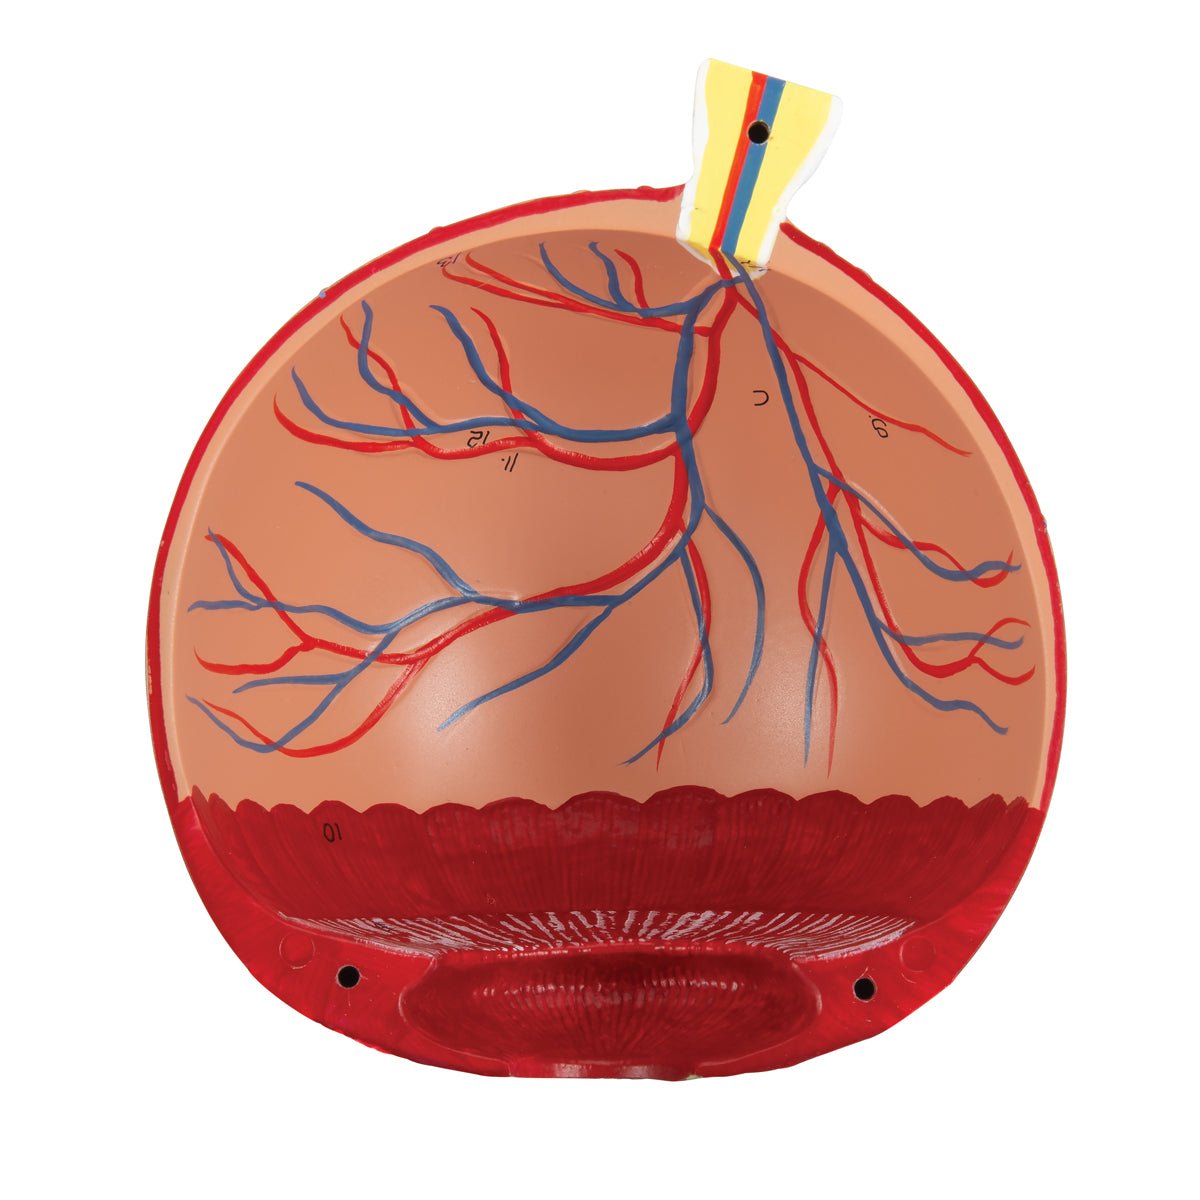

Anatomical models

Selling anatomical models is the mainstay of eAnatomi, although we also spend a lot of resources developing our own anatomical materials such as posters. Anatomical models are used for various purposes and can show both defined tissues, organs and organ systems. Are you looking for a simple model of bone tissue or perhaps an advanced torso model based on MRI technology, you can find it all at eanatomi.com.